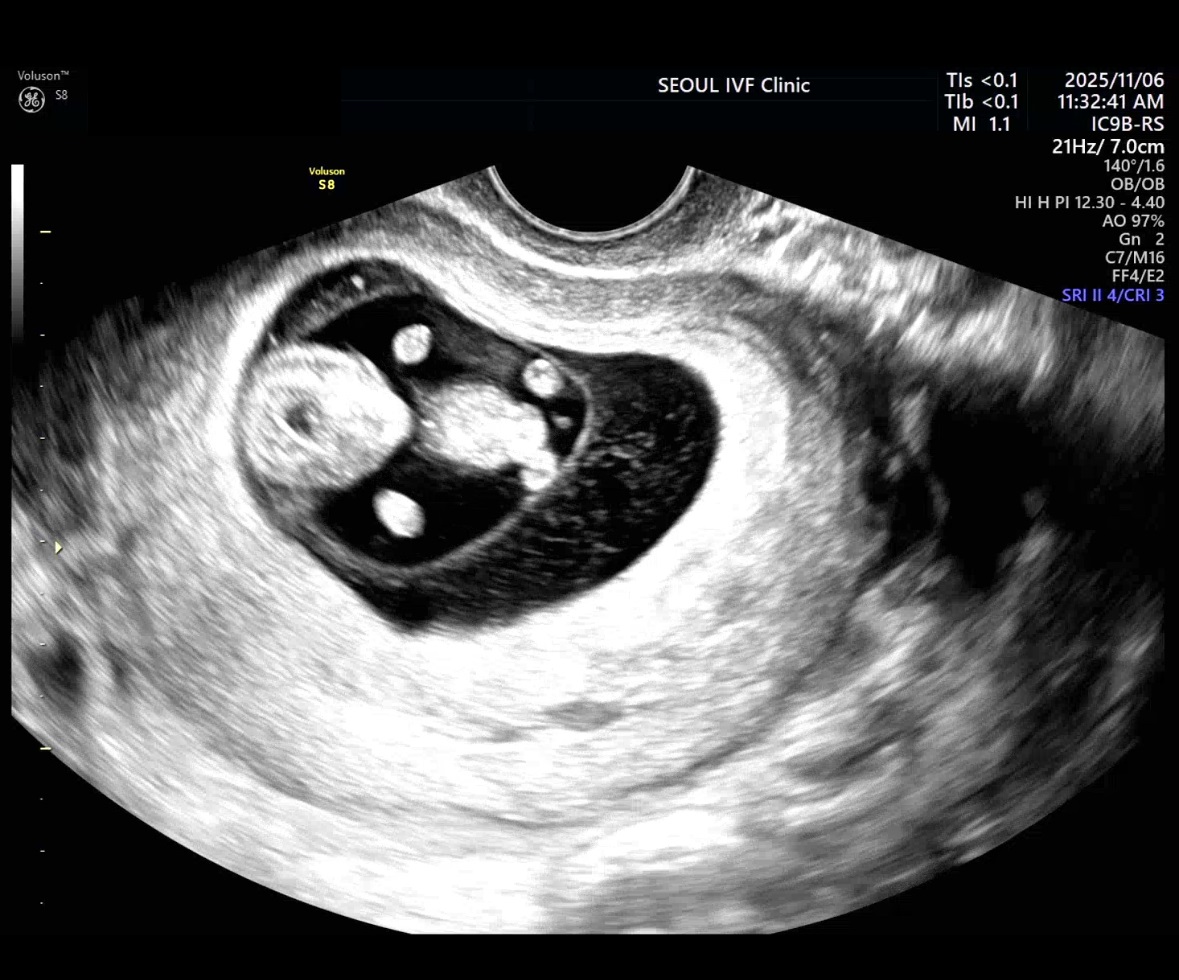

| 치료 도중 느꼈던 가장 기뻤던 순간과 절망적인 것들은 무엇인가요? 잊지 못할 경험이 있나요? | 처음 아기의 심장소리를 들었을 때가 가장 기뻤어요. 1차에 바로 성공해서 절망적이었던 순간은 없었습니다. |